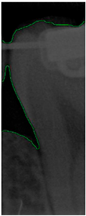

After training the YOLO object-detection models, this study tested unlabeled, and untrained the BW images. The test results are illustrated in Figure 10. The four object models used in this study, along with the image-augmentation technique, successfully identified all the teeth of interest in the BW images. After the image-segmentation stage, the extracted regions were delineated by the red boxes in Figure 10a, and the PR curve is shown in Figure 10b. The results extracted are depicted in Figure 11, effectively capturing the individual teeth and their edges and enabling further image-enhancement and CNN training steps.

Figure 11.

The results of tooth extraction based on YOLOv8.

This step aims to effectively separate the target of interest (individual tooth images) from the background (non-dental regions), as illustrated in Figure 4. This process involves multiple image-processing steps and identifies peaks and valleys for segmentation through accumulated pixel values. Considering that dental calculus symptoms often occur on both sides of the teeth, to enhance the effectiveness of CNN training, this study divided each tooth into two equal parts vertically.